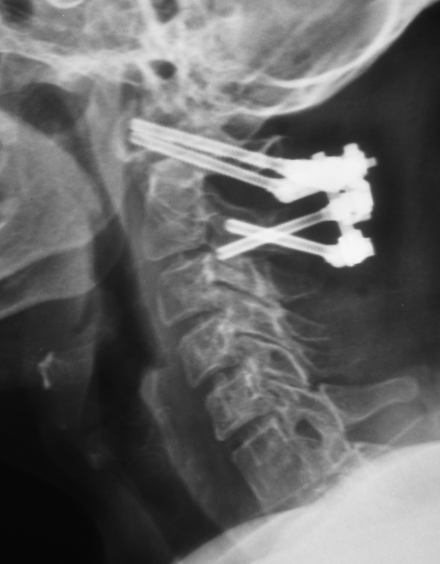

Postop Lateral Grafi - C1-C2 Fiksasyonu C1 Lateral Kitle Vidaları BT C2 Intralaminar Vidalar BT

Resim 5: Postop direkt grafi ve BT incelemelerinde C1-C2 seviyesindeki stabilizasyon sistemi görülmektedir. C1 seviyesinde lateral kitle vidaları (orta resim), C2 seviyesinde ise pediküller vida uygulaması için uygun olmadığından (yüksek seyirli vertebral arter) intralaminar vidalar kullanılmıştır (en sağdaki resim).